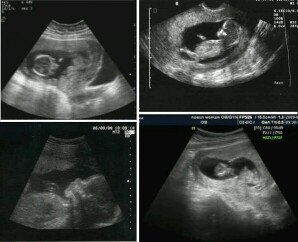

Sa tingin nyo ilang months na kaya ito?

Sainyo po ba ultrasound yan? May nakasulat nmn sa result kung ilang weeks or mos na si baby

4 months po cguro? May nakalagay nmn po kung ilang weeks yung baby pag inultrasound

2nd trim na yan between 4-6mos. 🙂

Ahmm.. Tingin ko 6-7 months

Para pong 4 months to 5

6 months

5-6 mons

6months

6